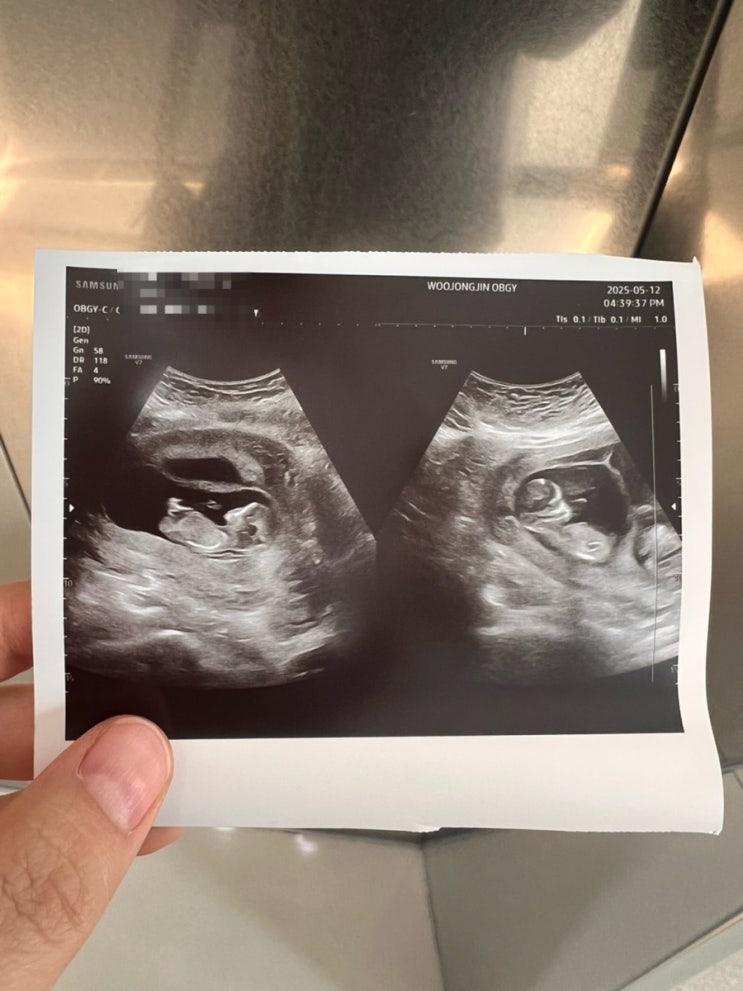

28. 13주5일 초기정밀초음파

초기정밀초음파 보러 김건우산부인과 가는날 여전히 갈색냉은 계속되고 이제 꼬리뼈 통증까지 온 나 아무래...